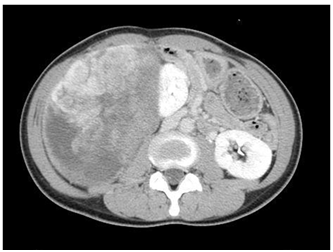

A 43year-old female noticed a mass in her abdomen about 1 month before she was referred to our hospital. The area just above the mass was tender, and the mass extended from the right upper abdomen to the lateral abdomen and was the size of a child’s head. No other findings were noted during physical examinations. A laboratory analysis produced almost normal results, and computed tomography (CT) and magnetic resonance imaging (MRI) revealed a large retroperitoneal tumor measuring 20×16cm occupying the entire abdominal cavity. The tumor had pushed the surrounding organs, such as the right kidney and liver, outwards (Figure 1). The right adrenal artery was the tumor’s main feeding artery, but many other arteries surrounded and fed the tumor (Figure 2). The tumor’s interior had a non-uniform structure; some areas exhibited early enhancement, whereas other areas were barely enhanced. There were no signs of distant metastasis or infiltration into the surrounding tissues. From the above findings, we initially suspected an adrenal tumor, but no conclusive diagnostic evidence was obtained. A further laboratory analysis produced the following results: adrenaline, 10pg/mL; noradrenaline, 189pg/mL; dopamine, <5pg/mL; cortisol, 17.1µg/d; aldosterone, 398pg/mL; dehydroepiandrosterone sulfate, 56µg/dL; plasma renin activity, 4.7ng/mL/h; urinary vanillylmandelic acid, 4.2mg/day; urinary metanephrine, 0.09mg/day; urinary normetanephrine, 0.24mg/day. These findings suggested that the mass was a non-functioning tumor. In addition, no accumulation was seen in the adrenal region on metaiodobenzylguanidine scintigraphy. Finally, we performed a complete surgical resection of the tumor and the right adrenal gland because of the possibility of malignancy and to relieve the patient’s symptoms. Macroscopically, the surgical specimen was 20.0x20.0x18.0cm in size and weighed 1.8kg. The mass was surrounded by a fibrous capsule and had not infiltrated into the surrounding tissue. A cross-section of the tumor showed a yellowish fibrous lobulated solid mass and some cysts (Figure 3). A pathological examination revealed that the tumor was composed of spindle-shaped cells, which were arranged in the “patternless pattern” and exhibited varying degrees of cellularity and low mitotic activity [1-2 mitoses per 10 high-power field]. Immunohistochemical staining detected positivity for CD34 and vimentin. On the other hand, the tumor was negative for c-kit, desmin, smooth muscle antigen (SMA), and S-100, which confirmed the diagnosis of a retroperitoneal SFTs. Based on the surgical findings, we suspected that the tumor was of mesenchymal origin; i.e., that it was derived from the nearby right adrenal gland. The patient did not suffer any complications and was discharged. No further treatments were performed, and 5years have passed without recurrence since the operation.

Figure 1 Macroscopic findings: Axial CT image of the abdomen at the mid abdomen level shows a large retroperitoneal tumor measuring 20×16cm was found. It occupied the entire abdominal cavity and had pushed the surrounding organs, such as the right kidney and liver, outwards.